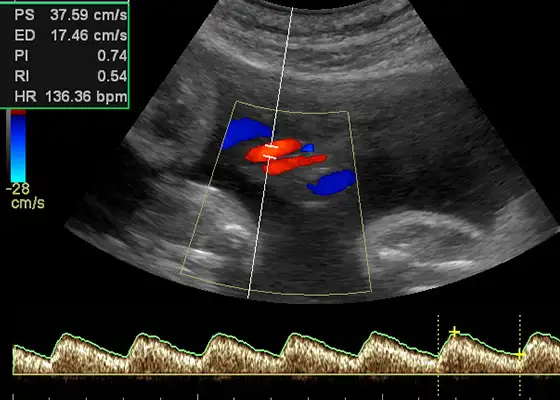

Farbdopplersonographie

Darstellung von Blutfluss und Gefäßstrukturen – wichtig für die Abklärung von Zysten, Myomen und anderen Veränderungen.

Farbdopplersonographie in der Praxis